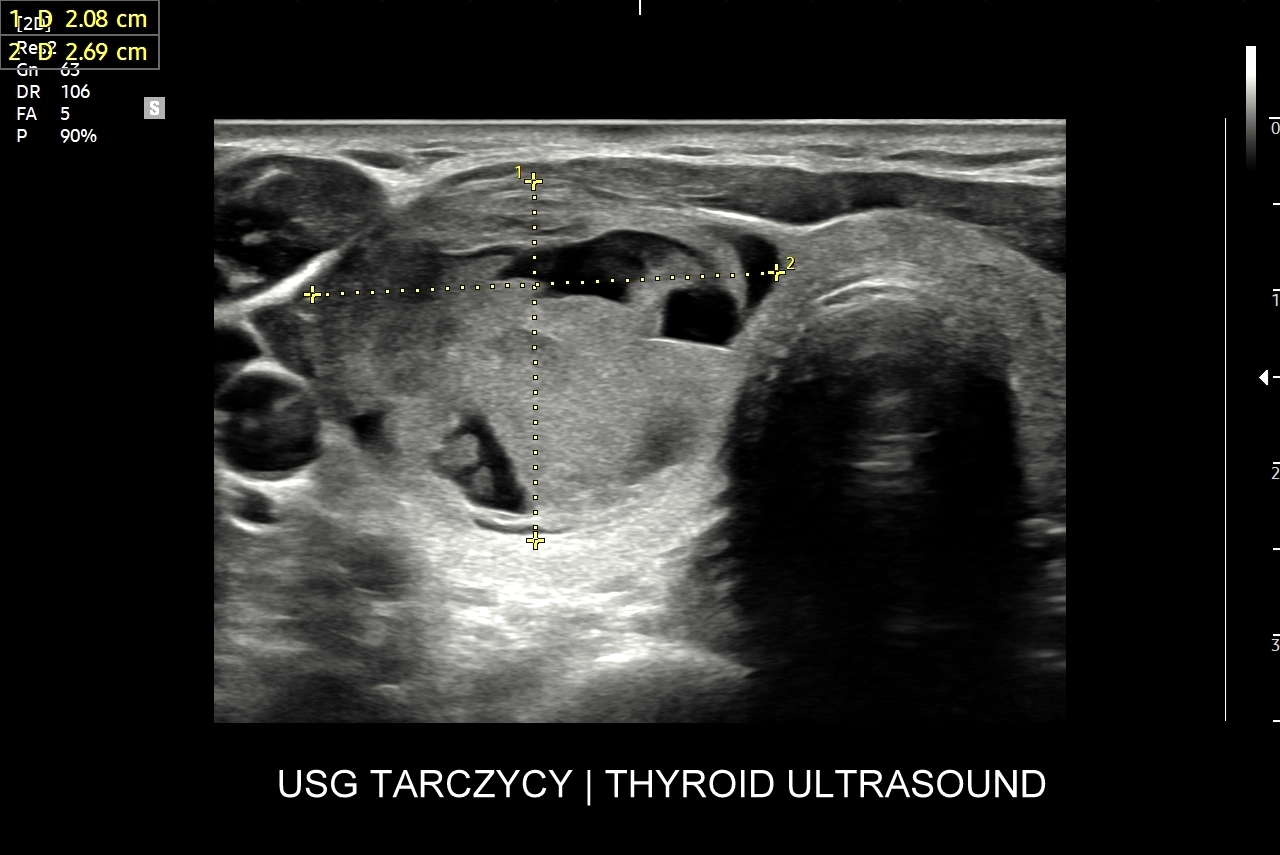

Czym jest guzek tarczycy? Guzek tarczycy jest określeniem dotyczącym uwypuklenia w zakresie szyi, które wywodzi się z gruczołu tarczowego. W potocznym języku jednakże pojęcie to odnosi się do tzw. zmian ogniskowych w tarczycy, tj. takich zmian, których wymiar można określić w trzech płaszczyznach. W obrębie zmian ogniskowych wyróżnia się torbiele oraz zmiany lite, w domyśle tkankowe.

Kiedy wykonać biopsję guzka tarczycy? Wskazania do wykonania diagnostycznej, aspiracyjnej biopsji  cienkoigłowej guzka tarczycy określa się na podstawie skali TIRADS (ang.  thyroid image reporting and data system). Istnieją skale TIRADS amerykańska, europejska oraz polska modyfikacja skali europejskiej (EU-TIRADS-PL). W każdej z wymienionych oceniane są różnorodne cechy zmiany ogniskowej tarczycy takie jak rozmiary, echogeniczność, struktura wewnętrzna, kształt, orientacja, obecność mikrozwapnień, zarysy, cechy naciekania. W skali TIRADS wyróżnia się 5 kategorii, a im wyższa kategoria tym wyższe ryzyko obecności raka. Biopsję guzka tarczycy przeprowadza się począwszy od kategorii 3, przy czym pod uwagę bierze się również wielkość guzka.